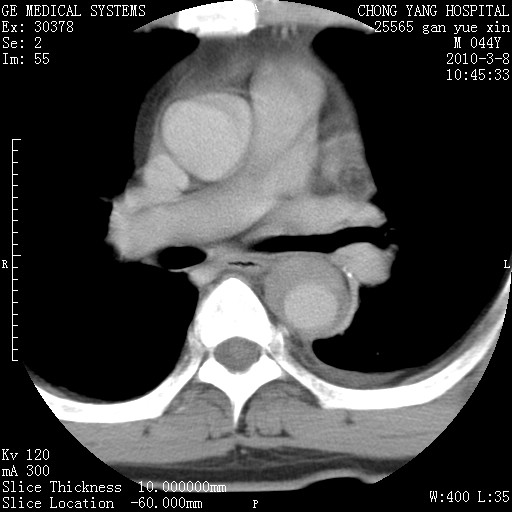

标题: CT24940:主动脉增强,典型病例。 [打印本页]

标题: CT24940:主动脉增强,典型病例。

夹层动脉瘤。

动脉夹层

夹层动脉瘤,典型

主动脉夹层。

动脉夹层的分型:

⒈debakey分型:根据主动脉夹层累及部位,分为三型:ⅰ型:原发破口位于升主动脉或主动脉弓部,夹层累及升主动脉、主动脉弓部、胸主动脉、腹主动脉大部或全部,少数可累及髂动脉。ⅱ型:原发破口位于升主动脉,夹层累及升主动脉,少数可累及部分主动脉弓。ⅲ型:原发破口位于左锁骨下动脉开口远端,根据夹层累及范围又分为ⅲa,ⅲb。ⅲa型:夹层累及胸主动脉。ⅲb型:夹层累及升主动脉、腹主动脉大部或全部。少数可累及髂动脉。

⒉stanford分型:a型:夹层累及升主动脉,无论远端范围如何。b型:夹层累及左锁骨下动脉开口以远的降主动脉。

夹层动脉瘤,少量胸水

夹层动脉瘤;左侧少量胸腔积液。

典型主动脉夹层。